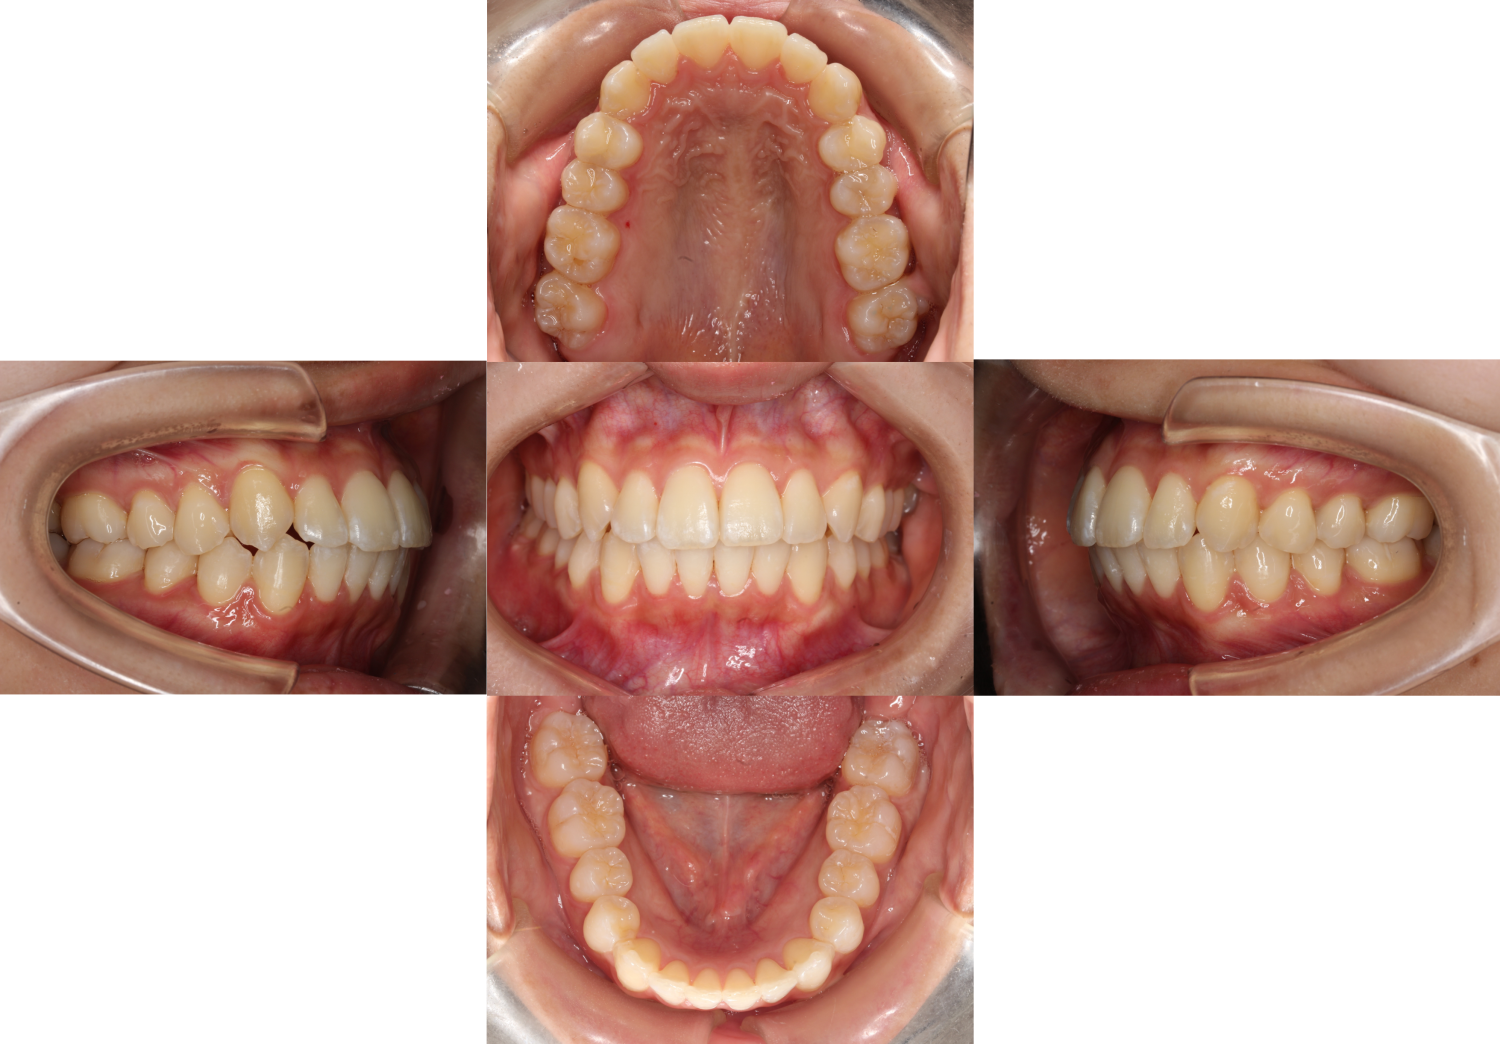

上下の歯に装置を装着しました。

こちらの患者様はIPRと呼ばれる処置を行いながら並べていきます。

IPRは、上下で歯の大きさのバランスが違ったり、ガタガタがある際によく使われます。

具体的には、歯と歯の間をヤスリがけしてスペースを作る処置です。